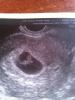

Сходила на повторное узи, посмотреть как там отслойка. Ну что сказать, во первых в той клинике где делала узи в тот раз, мне уже заходить и увидела что мужик узист и отказалась 😂ну не могу я так ... Пошла в другую, и вообщем есть эмбрион живой, сердечко бьется, как врач сказала еще как бьется)))) единственное отслойка все таки осталась небольшая и еще какая то свободная жидкость за маткой, не пойми что ... Сегодня иду на учет вставать, посмотрим что врач скажет 😊а так моя кнопка такая прям ми ми ми, врач сказала , что конечно это не точно, но по опыту , по эмбриону можно сказать что девочка ( узист очень старая в возрасте, я еще с первой 10 лет назад к ней ходила ) )) ну вот посмотрим 😊 срок 7-8 недель

@kipasa1990, я сама теперь незнаю((( две недели назад по узи было 3 недели, сегодня уже 7-8, а по месячным ваще 9, 23.10.14 было, вообщем фиг знает какой срок у меня